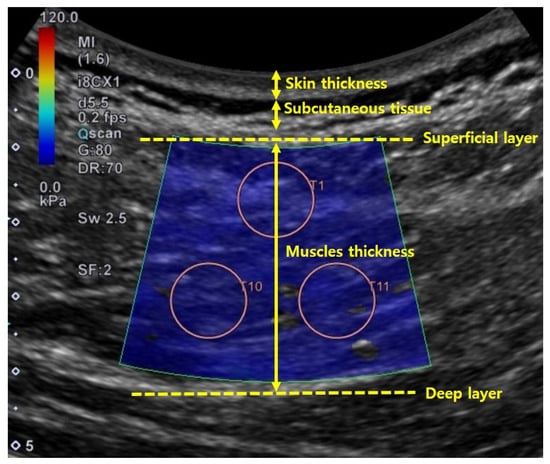

Each shear elastic modulus of the aforementioned muscles was evaluated by measuring shear-wave propagation speed in the tissue, which was generated using SWE at each measurement posture. The circular regions of interest (ROIs) were set in the color-coded boxes on the SWE mode (Figure 3). Three circular ROIs with a diameter of 10 mm were set in the color-coded box, with one located at the top–center of the box and the other two located at the inferior to the first-assigned circular ROI (Figure 3) [21,24]. Shear elastic modulus at the set ROI was automatically calculated from the ultrasound imaging device. The mean shear-elastic-modulus values of the three circular ROIs were calculated for each muscle per posture for five images. ROIs were determined by the same examiner.

Figure 3. Example for setting regions of interest to measure shear elastic modulus in different postures on flat and Wilson table. In this case, erector spinae 1 located at L3–4 is shown: (a) flat table; (b) Wilson table.

Skin and muscle thicknesses were measured from the collected shear-wave ultrasound images using Image J 1.52a (National Institutes of Health, Bethesda, U.S.). Skin thickness was measured as the distance (cm) between the surface of the epidermis and the subcutaneous tissue. Muscle thickness was measured as the distance between superficial and deep muscle facias. Both skin and muscle thicknesses were measured by drawing a straight line through the center of the image [26] (Figure 4). Skin and muscle thicknesses were measured using one shear-wave ultrasound image per muscle and condition.

Figure 4. Method used to determine skin and muscle thicknesses in ultrasound image.